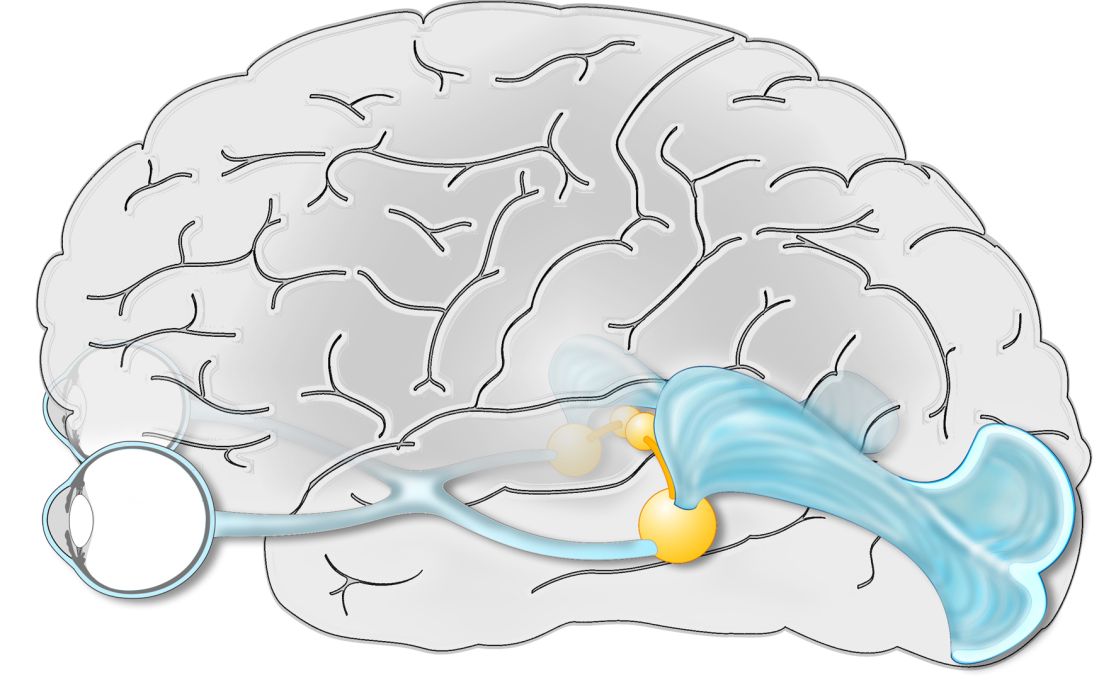

Zeichnung von einem Gehirn

FUN-Kurs und FUN-Kurs plus

Der Kurs richtet sich an interessierte augenärztliche Fachkräfte und das in der gebietsärztlichen Weiterbildung befindliche Kollegium, die ihr Wissen über neuroophthalmologische Krankheitsbilder vertiefen wollen.